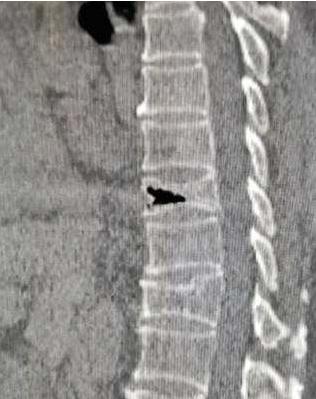

仔细跟患者讲了讲保守治疗的风险:1.心脑血管意外,2.压迫神经出现下肢瘫痪风险,3.再骨折风险,4.深静脉血栓致死风险,5.骨折不愈合风险,6.压疮、褥疮、坠积性肺炎风险等等巴拉巴拉说了一通,朋友表示明白了,以为这个事情就这么过去了,三个月后的一天朋友联系我说老太太因为慢性支气管炎住到呼吸科了,让我看看老太太腰好了没有,我让他查个腰椎CT再喊我去看。

果不其然,骨折没有愈合,仔细追问病史,三个月没有严格卧床,另外因长期卧床老太太出现了坠积性肺炎...(这个朋友又一次选择了治疗并发症),当时仔细交代风险了,完全没理解,老太太把骨折的常见两个并发症都进行内科治疗了,便秘(胃肠蠕动减慢)和肺炎(坠积性肺炎),问我怎么办?我实在看不下去了,直接明确告诉他手术,别再折腾了,老太太再折腾可能就坚持不住了(老人卧床半年基本上就起不来了),朋友终于决定手术了。

椎体成形术,没什么特殊的,常规手术微创操作。术前复查腰椎MRI时又提出异议了,三个月前查的MRI为什么还要查?无力吐槽,对我完全不信任,仔细讲解除外新发骨折,那不是查了腰椎CT了吗?再次解释除外隐匿性骨折(感觉医生并不是在看病,天天在解释)。果不其然,三个月前腰椎骨折,这次不光腰椎骨折,胸椎也有骨折(朋友并没有理解到苦心),局麻微创手术很顺利,两个小时后安返病房,患者腰痛背痛明显好转。